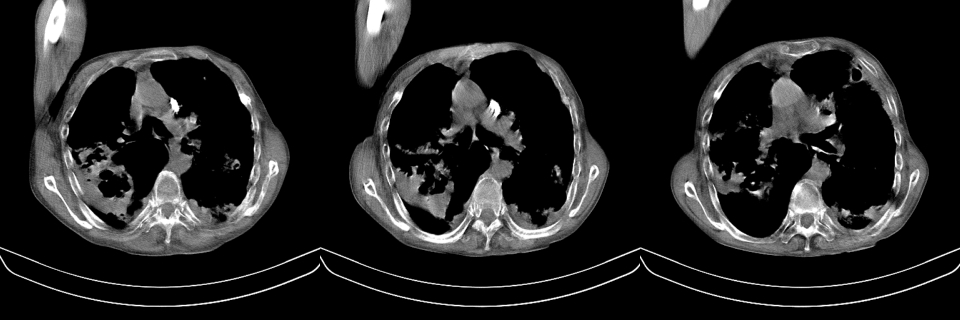

以下是引用mzh123在2007-8-26 19:58:00的发言:[br]两肺弥漫性斑片改变,其中可见大小不等之不规则空洞,结合既往病史还是考虑结核复发及感染。

以下是引用云翔在2007-8-26 20:54:00的发言:[br]这是44岁的肺吗?是否有先天病的基础?干酪性肺炎?